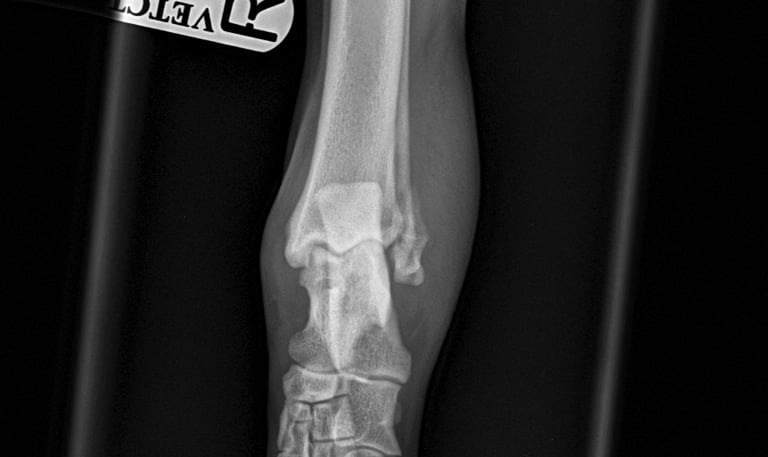

Case 2 - Buddy

Lateral malleolus fracture - Golden retriever, 2y male